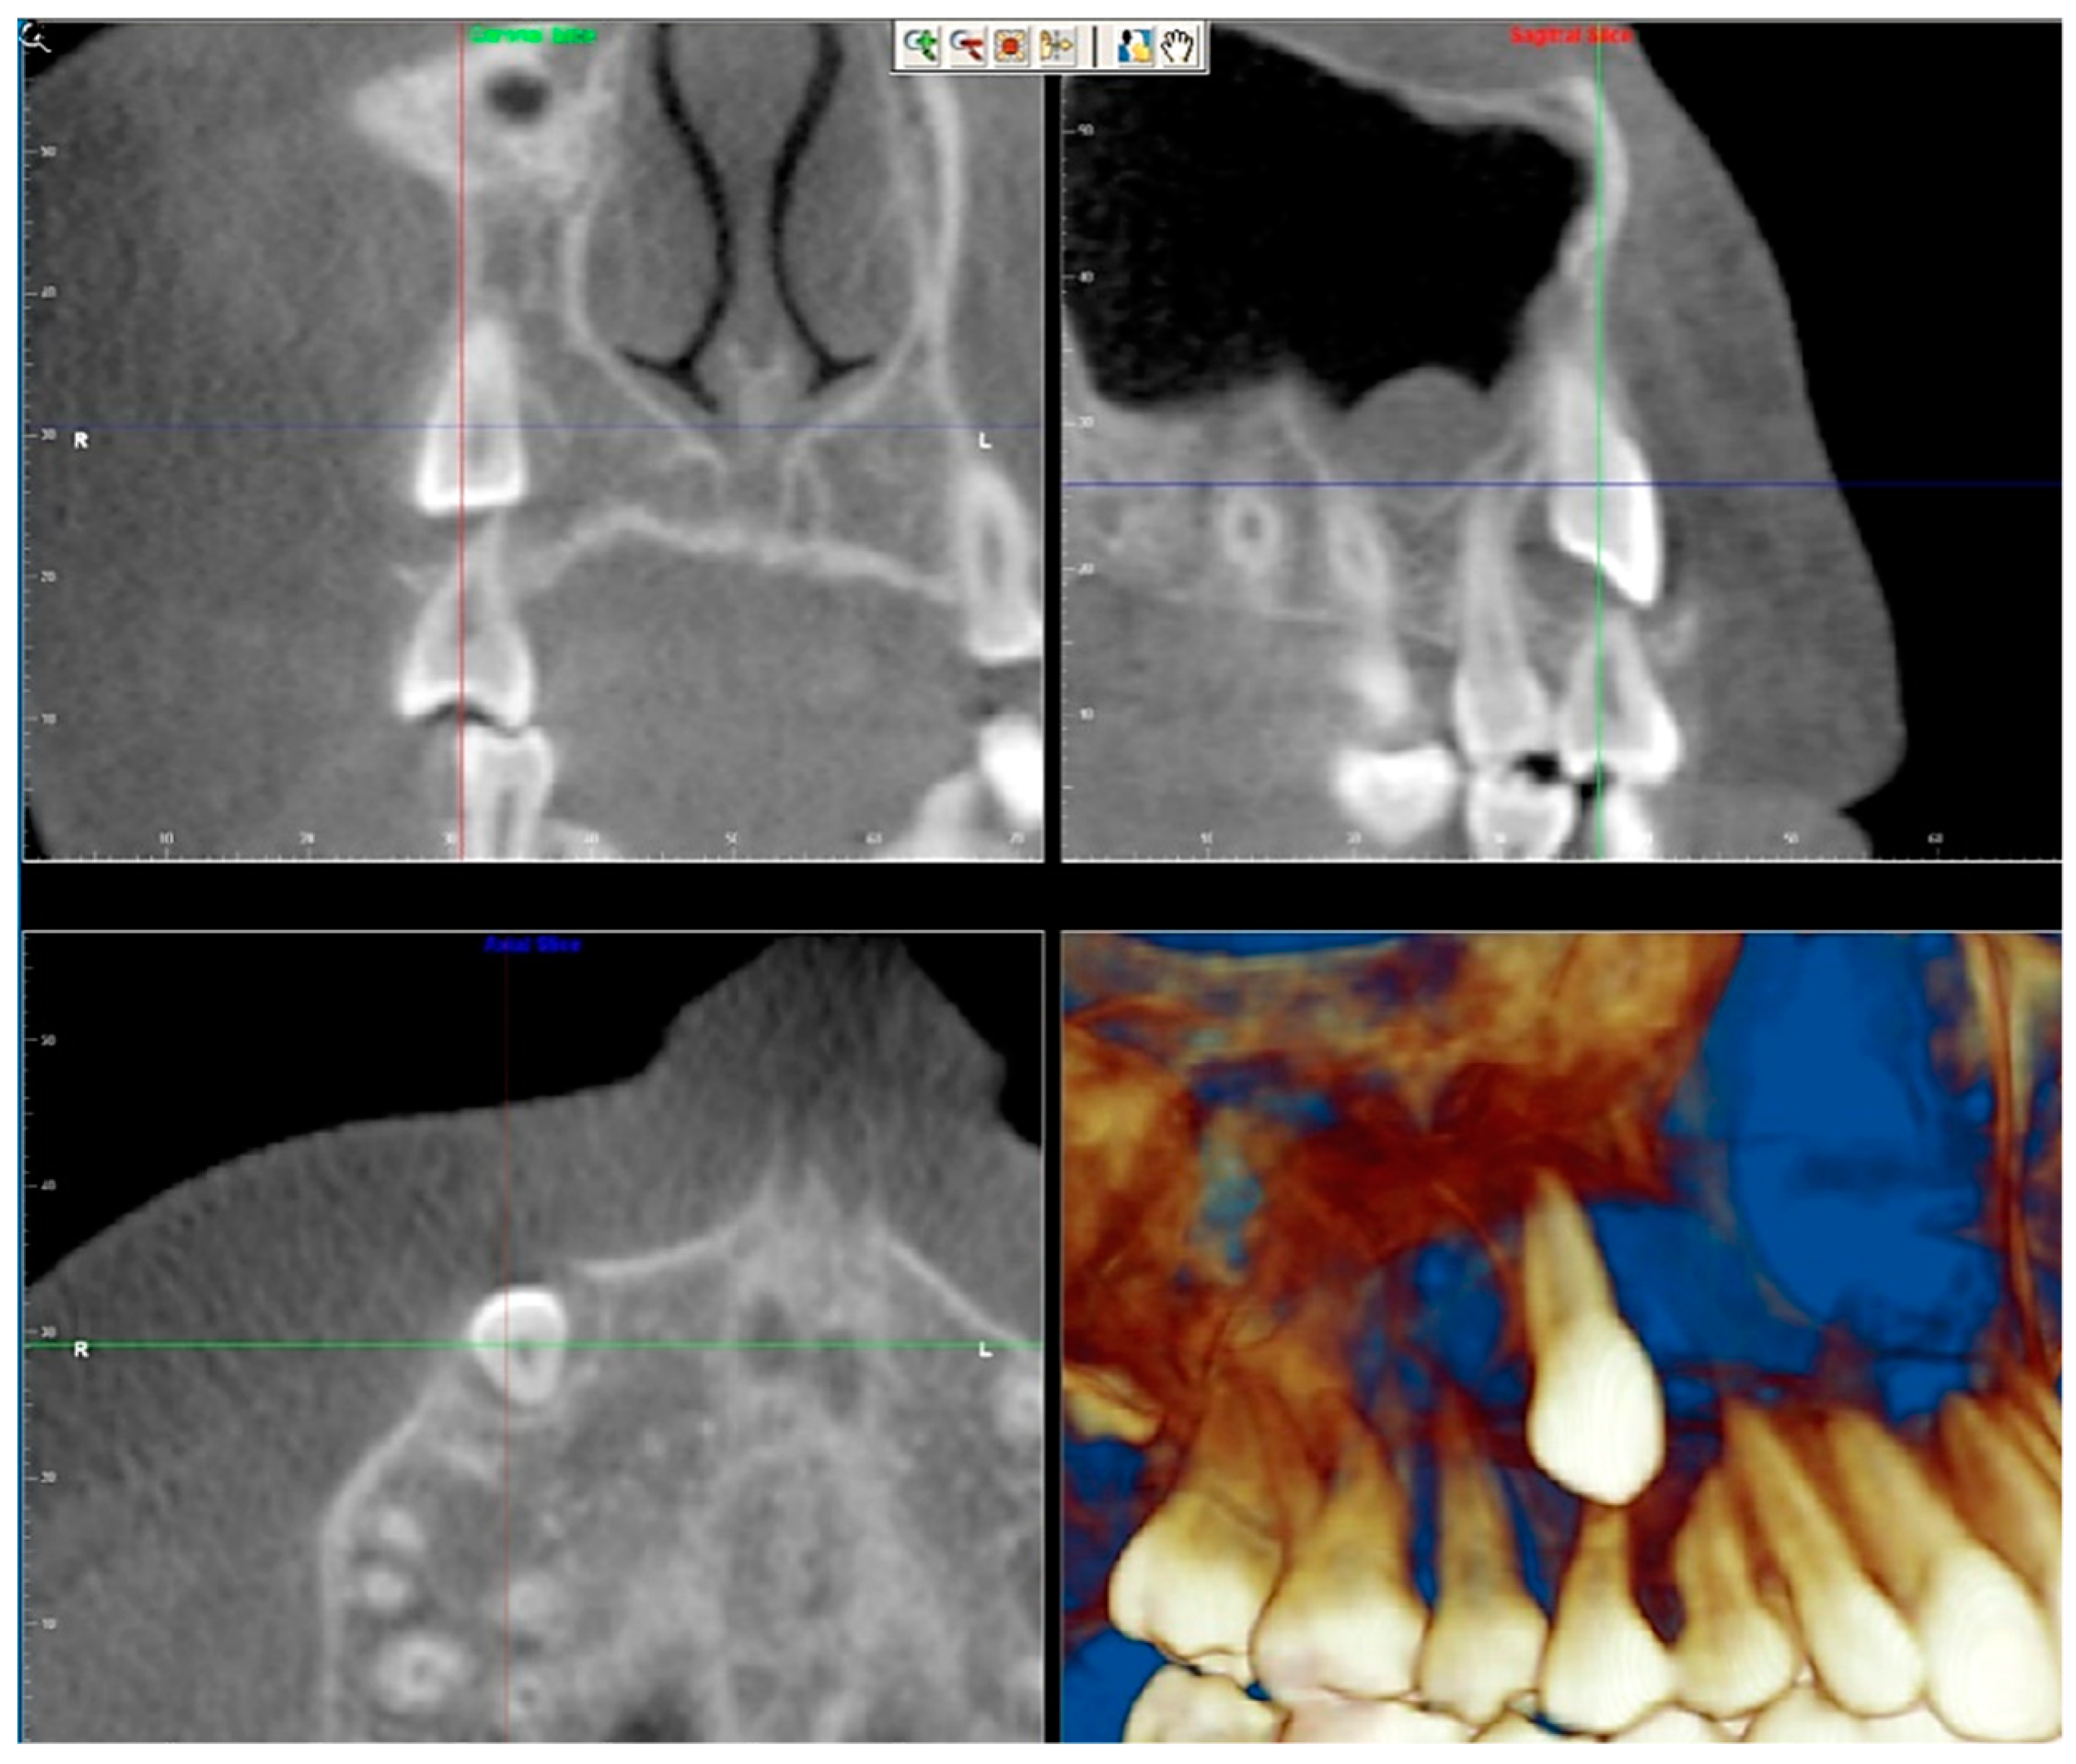

- Assessment of proposed sites of temporary anchorage device (TAD). Figure 11, Figure 12, Figure 13 and Figure 14 show correction of the Class II molar relationship using a temporary anchorage device. Figure 11 shows a pre-treatment intraoral photograph of the right side. The Class II molar relationship can be observed. Figure 12 shows coronal, sagittal and axial views, as well as a volume rendering of CBCT that was acquired in order to assess the site of the temporary anchorage device. Figure 13 shows an intraoral photograph of the right side, in which the TAD was placed mesial to the maxillary first molar, and a power chain was attached from this TAD to a hook placed distal to the lateral incisor. Figure 14 shows a post-treatment intraoral photograph showing improvement of the Class II molar relationship after removal of all orthodontic appliances.